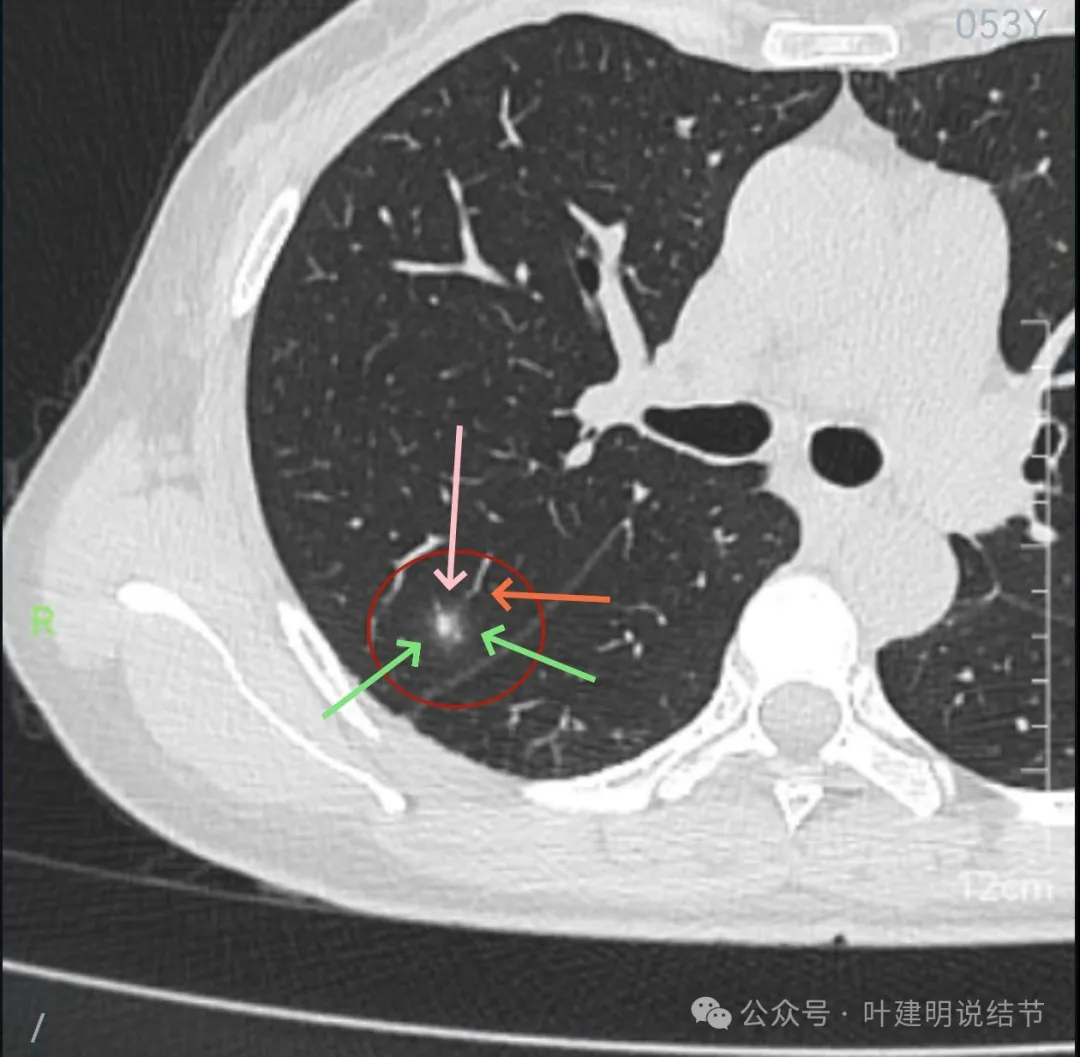

先来看2024年10月16日的影像:

右上后段混合密度结节,瘤肺边界欠清,有明显实性成分,边缘不光滑。

右肺很淡的磨玻璃阴影,伴进入的血管异常增粗,整体轮廓尚显清楚。

右下叶背段边界欠清的磨玻璃影,有血管刚好位于病灶处。

病灶出现,轮廓不清,瘤肺边界模糊,有血管穿行,血管有异常增粗。

血管壁有异常密度增高,病灶混合密度,轮廓总体在此层较清,但瘤肺边界不清。

病灶偏实性部分不密实,磨玻璃部分过淡且模糊。

边缘有毛刺,但不够锐利;外周磨玻璃成分密度过淡且界限不清;实性部分也显得不致密;与叶间裂距离近但没有任何牵拉影响。

实性成分在灶内看,也是界限不清,磨玻璃部分淡而糊。

整体感觉像病灶中间偏实性些的成分伴外周晕征。

边缘区域离叶间裂更近,仍无牵拉。

几乎贴着叶间裂了,仍无任何牵拉影响。

病灶密度边缘部分也不均,离叶间裂近而没有影响。

上图病灶已经贴着叶间裂,但仍显示是平直的,没有任何牵拉影响。